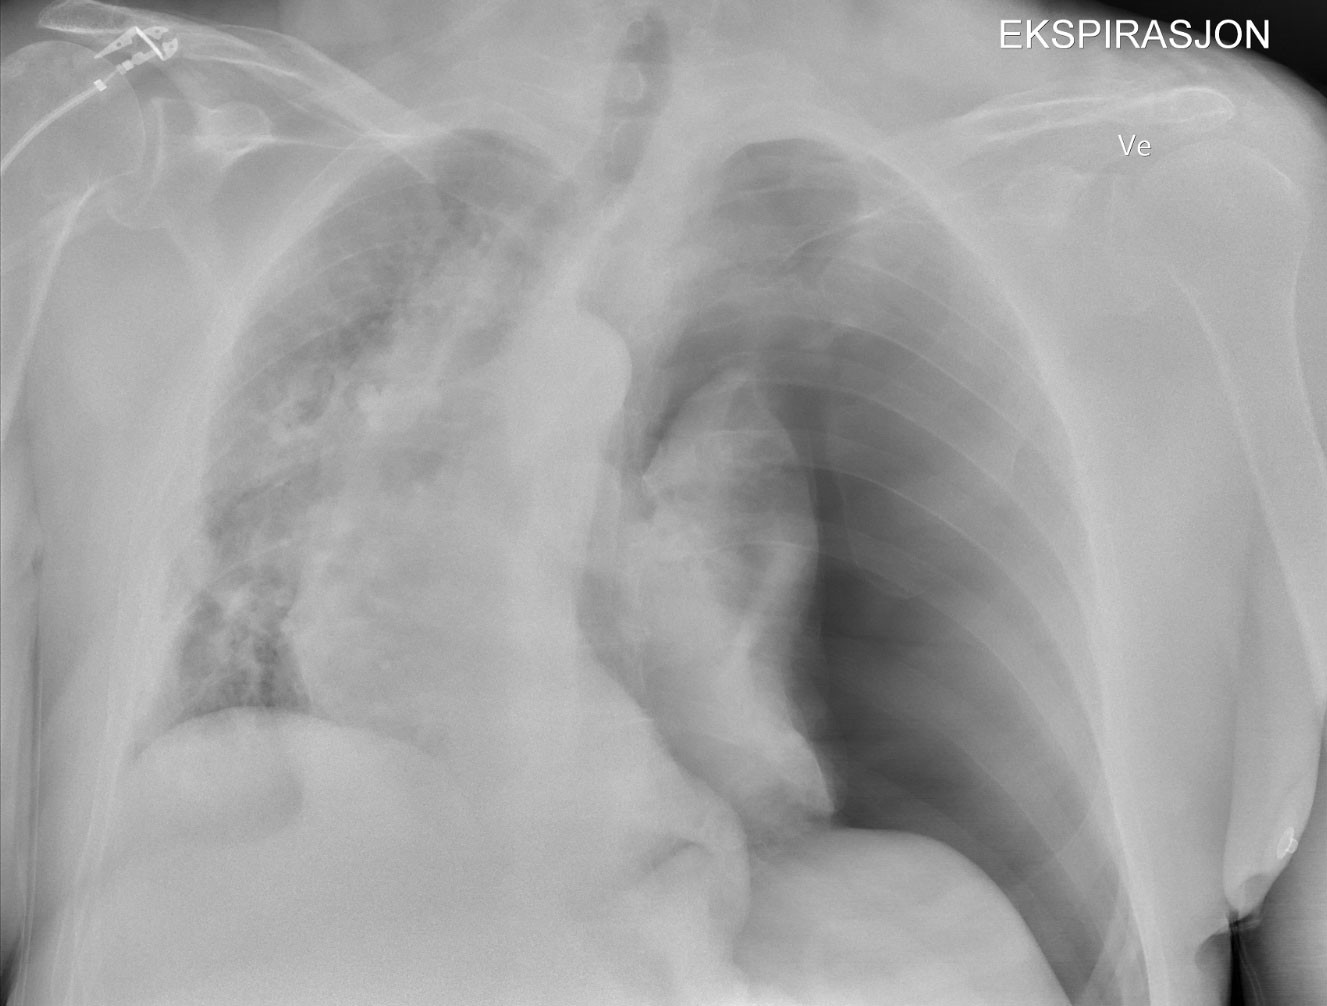

One hour before the end of the operation, oxygen saturation dropped to 89 %, tidal volume from 550 ml to 366 ml, and mean blood pressure from 70 mmHg to 60 mmHg. Oxygen in inspired air was increased from 40 % to 100 %, and inspiratory pressure was increased from 9 cm to 18 cm of water. Oxygen saturation rose to 91 % and blood pressure remained unchanged. No lung auscultation or blood gas analysis were performed. Surgery was completed, anaesthesia was stopped and the laryngeal mask was removed without difficulty. Upon arrival at the postoperative ward, oxygen saturation was 88 % despite the application of a non-rebreather oxygen mask. The patient was dyspnoeic, clammy and pale, with blood pressure of 90/60 mmHg. The duty anaesthetist was immediately called. In an ultrasound scan a few minutes later, the anaesthetist found an absence of lung sliding of the left pleural blades. Chest x-ray confirmed left-sided tension pneumothorax (Figure 1).

Under local anaesthesia, the surgeon placed a 12 French Portex chest drain in the fifth intercostal space in the operating room 1.5 hours after the shoulder surgery. The lung re-expanded after two hours with 5 mmHg suction. In the intensive care unit three hours after surgery, the patient needed pain medication, but his blood pressure had normalised and the oxygen supply was reduced from 6 L to 2 L via nasal cannula. The thoracic drain was removed after 15 hours, and the patient was discharged 24 hours after surgery. At the six-month check-up, he was symptom-free and active.